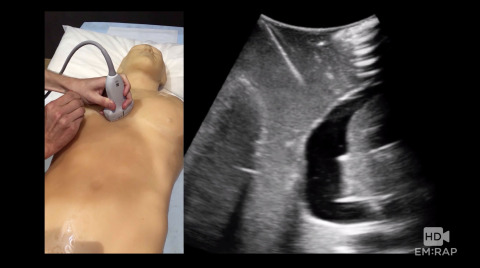

Ultrasound of ROSC

Jailyn Avila reviews the different ultrasound findings that can change your management during a code.